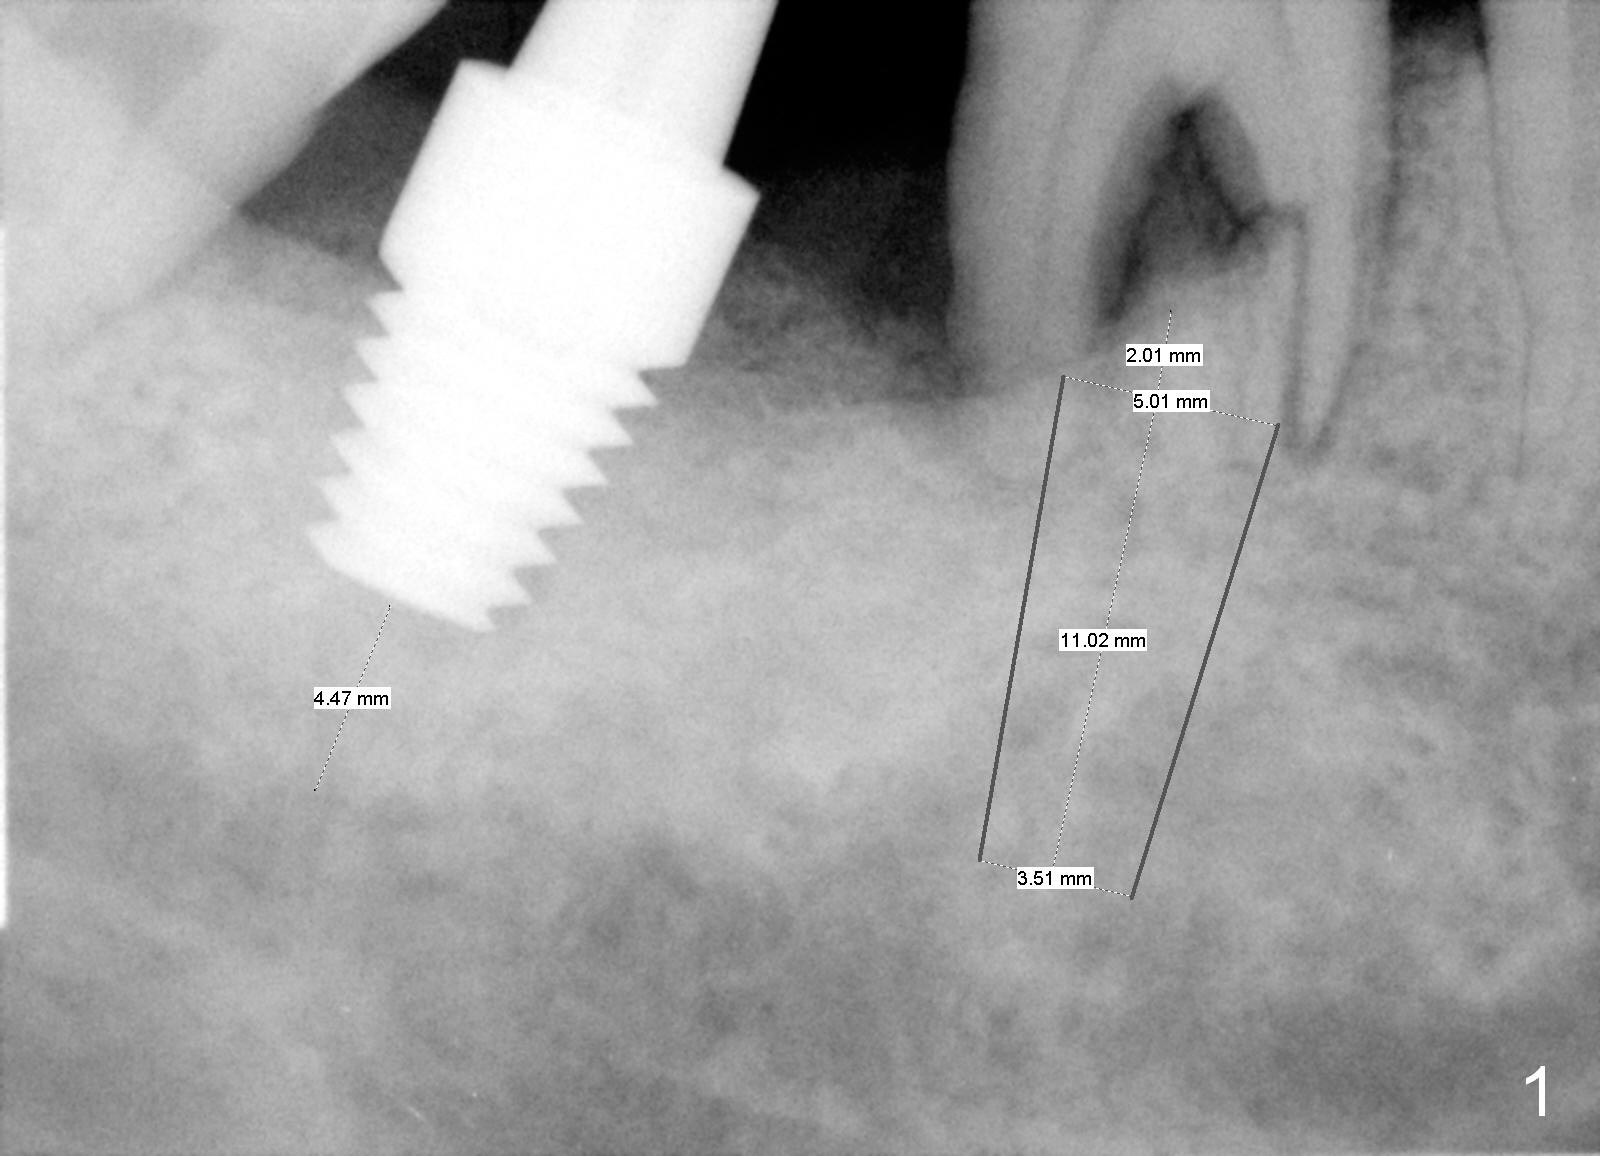

A 64-year-old man has pain at night, possibly associated with vertical fracture of the mesial root of the tooth #30, 1.5 years post cementation at #31 (Fig.1,2 (2 weeks post #7 implant placement). After extraction without antibiotic socket treatment, use medium Rongeur to even the irregular septal crest (Fig.3 red line) prior to using 1.6 mm pilot drill. The initial depth will be 13 mm. PA will be taken to confirm the apical position relative to the Inferior Alveolar Canal. An implant is placed at the distal and septal crestal level with bone graft in the distal socket, while the implant is well below the the mesial crest. The implant should be not too big. Make sure that the larger abutment does not touch the mesial crest. Since the entrance to the mesial socket is smaller than that of the distal, bone graft is placed in the mesial socket prior to abutment placement.